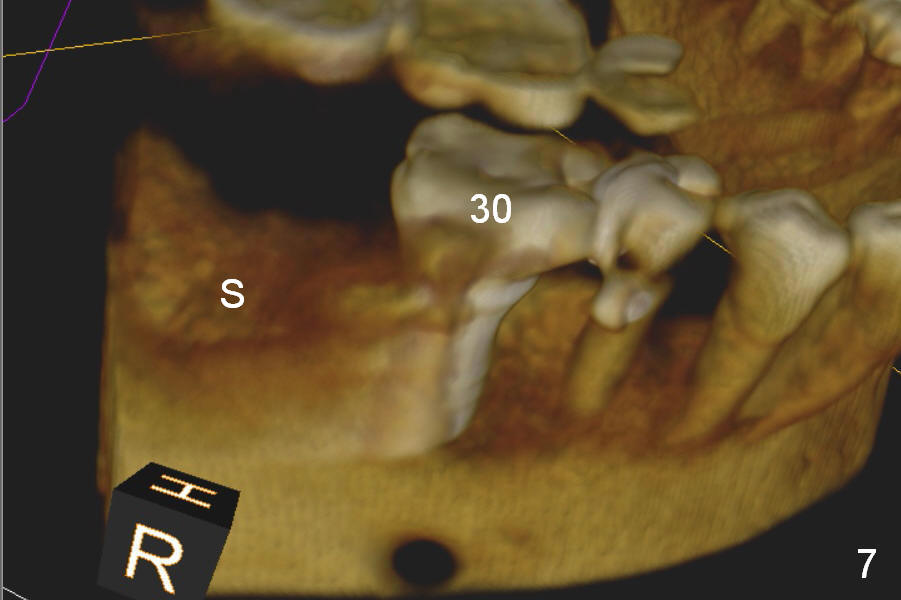

A 75-year-old man has apparent history of bruxism. The distal root of the tooth #31 had vertical fracture after root canal therapy. The tooth was extracted ~ 2 months ago while he returned to home country. It appears that there is buccal plate atrophy (Fig.1 S: socket).

Preop CBCT shows that a 6.4x10 mm implant is appropriate if placed in the middle of the socket (septum), 6 mm from the crown of #30 (Fig.5). Coronal section confirms that because of the lingual slope of the socket, osteotomy should be placed lingually (Fig.6 red line). Three-D image is shown in Fig.7.